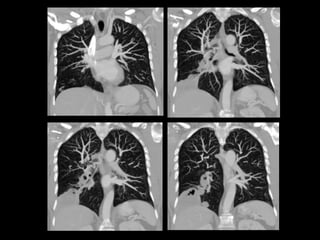

Varón de 56 años que consulta por hemoptisis

Protocolo AngioTC Torácico

• Desde base cuello hasta nivel de arterias renales

para incluir troncos supraaórticos y arterias

infradiafragmáticas.

• 0.8/1 mm. grosor de corte

• 100-120 ml contraste yodado no iónico a 4cc/sg.

• ROI en Aorta descendente.

• Reconstrucciones multiplanares y volumétricas

(MIP y VR): coronales (arterias mamarias internas

e intercostales) y axiales (arterias frénicas

inferiores y tronco celiaco).